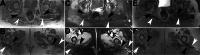

Multifocal desmoid-type fibromatosis (DTF) is very rare and usually regional. We report three cases that initially appeared to be multifocal, but subsequent detailed imaging revealed unsuspected tracking along nerves in two cases. This neural spread is reminiscent of neuromuscular choristoma (NMC), a rare developmental lesion in which mature skeletal muscle cells, or rarely smooth muscle cells, infiltrate and enlarge peripheral nerves. NMC is frequently associated with DTF. These two cases suggest that DTF spread along nerves and appeared as distinct multifocal lesions while actually being contiguous. The third case was felt to represent true multifocal tumor development, possibly due to tumor seeding at the time of chest surgery. The relationship of DTF to NMC is discussed.